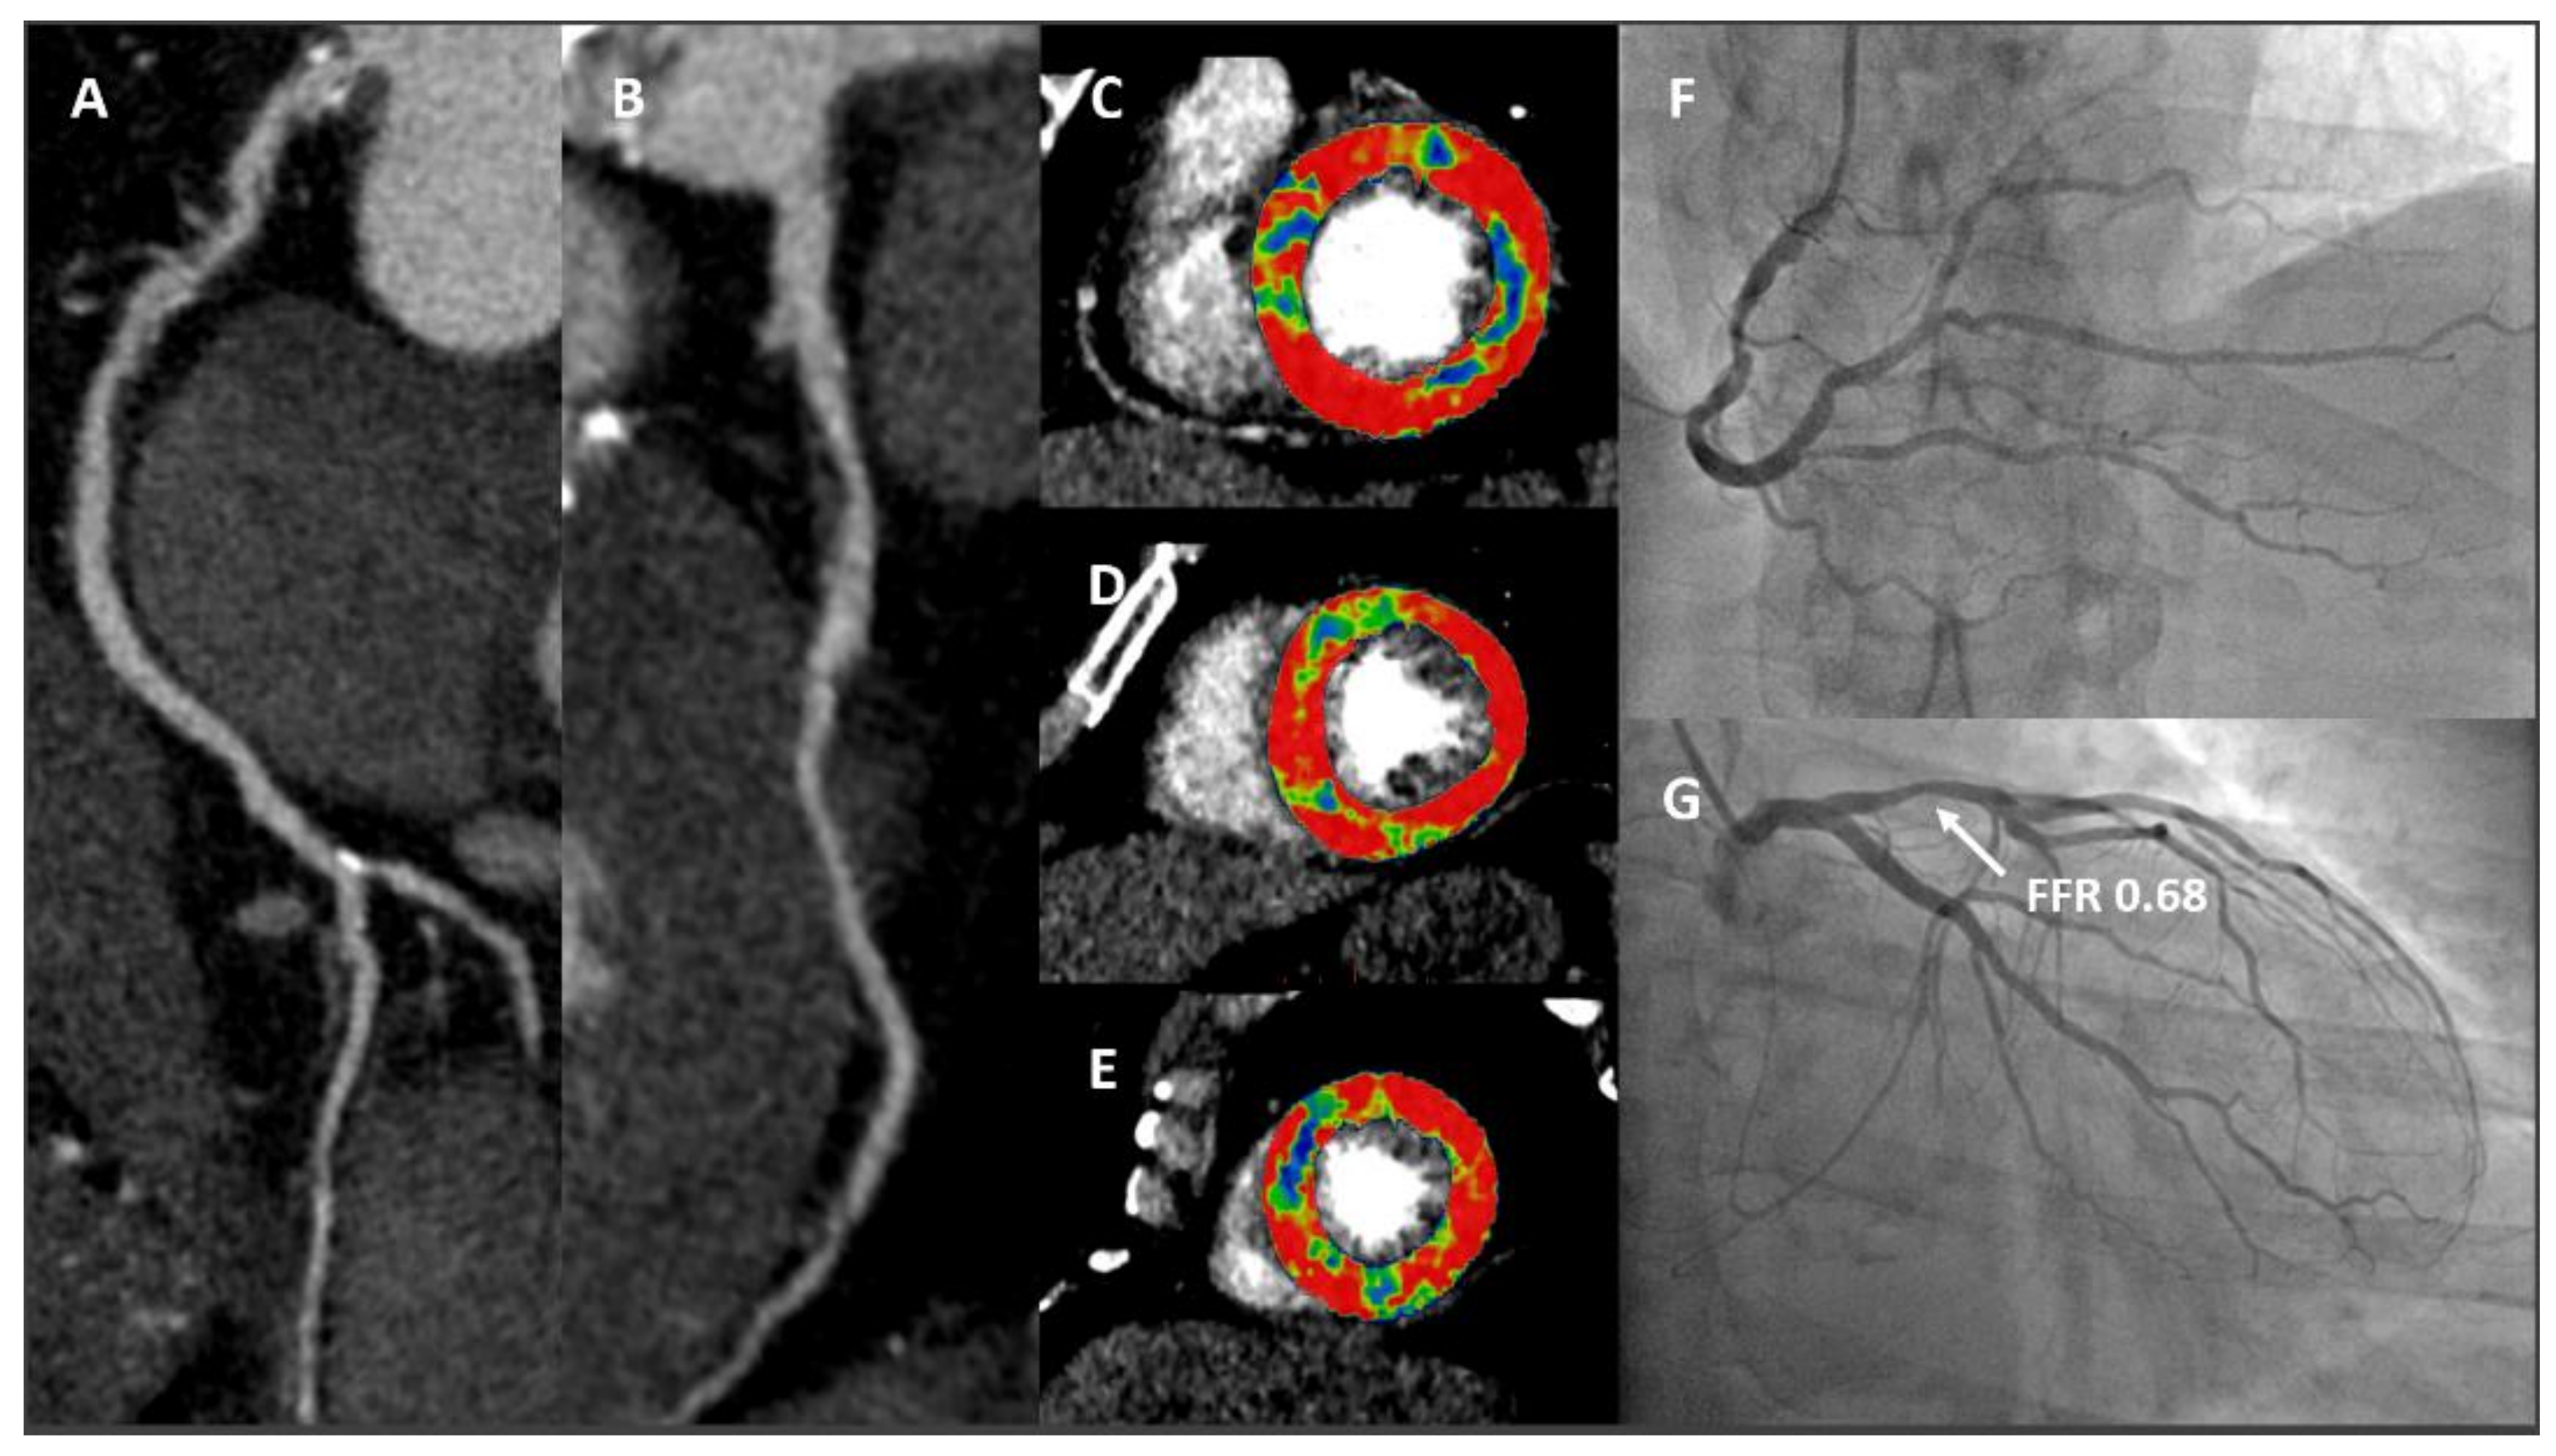

- Pontone, G.; Baggiano, A.; Andreini, D.; Guaricci, A.I.; Guglielmo, M.; Muscogiuri, G.; Fusini, L.; Soldi, M.; Del Torto, A.; Mushtaq, S.; et al. Diagnostic accuracy of simultaneous evaluation of coronary arteries and myocardial perfusion with single stress cardiac computed tomography acquisition compared to invasive coronary angiography plus invasive fractional flow reserve. Int. J. Cardiol. 2018, 273, 263–268. [Google Scholar] [CrossRef]

- Pontone, G.; Andreini, D.; Guaricci, A.I.; Baggiano, A.; Fazzari, F.; Guglielmo, M.; Muscogiuri, G.; Berzovini, C.M.; Pasquini, A.; Mushtaq, S.; et al. Incremental Diagnostic Value of Stress Computed Tomography Myocardial Perfusion With Whole-Heart Coverage CT Scanner in Intermediate- to High-Risk Symptomatic Patients Suspected of Coronary Artery Disease. JACC Cardiovasc. Imaging 2019, 12, 338–349. [Google Scholar] [CrossRef]

- Pontone, G.; Baggiano, A.; Andreini, D.; Guaricci, A.I.; Guglielmo, M.; Muscogiuri, G.; Fusini, L.; Soldi, M.; Del Torto, A.; Mushtaq, S.; et al. Dynamic Stress Computed Tomography Perfusion With a Whole-Heart Coverage Scanner in Addition to Coronary Computed Tomography Angiography and Fractional Flow Reserve Computed Tomography Derived. JACC Cardiovasc. Imaging 2019, 12, 2460–2471. [Google Scholar] [CrossRef]

- Baggiano, A.; Fusini, L.; Del Torto, A.; Vivona, P.; Guglielmo, M.; Muscogiuri, G.; Soldi, M.; Martini, C.; Fraschini, E.; Rabbat, M.G.; et al. Sequential Strategy Including FFRCT Plus Stress-CTP Impacts on Management of Patients with Stable Chest Pain: The Stress-CTP RIPCORD Study. J. Clin. Med. 2020, 9, 2147. [Google Scholar] [CrossRef]